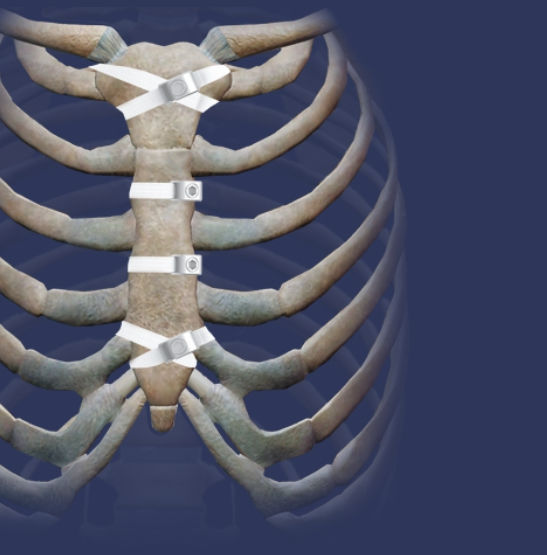

Figure 1Sternal plating for primary and secondary sternal closure; can What Are Sternal Wires Made Of three sternal wires are used prior to using the plates: sternal wires closure of a midline sternotomy incision using wires is the standard method used for decades. Sternum wires are used during a. learn about the use of rigid sternal fixation as an alternative to sternal wires for reduced pain and accelerated recovery from dr. As the. What Are Sternal Wires Made Of.